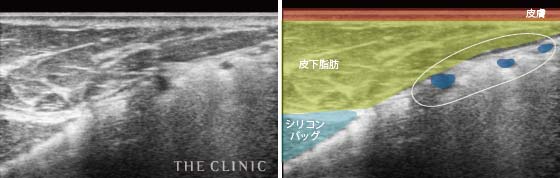

乳腺や脂肪、筋肉などの層の状態をみることができるので、シリコンバッグのまわりにある皮膜の厚さや石灰化の状態だけではなく、シリコンバッグが挿入されている正確な位置やシリコンバッグの破損なども確認することができます。

- シリコンバッグ破損(皮膜外破裂)

- 破裂によって皮膜の外(お腹の上部)へ流出したシリコン